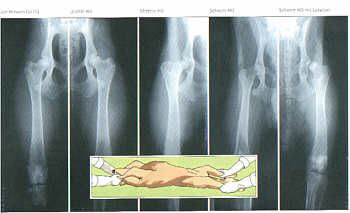

Röntgenbilder von Hüftgelenken zur Diagnose

Röntgenbilder von Hüftgelenken zur Diagnose der Hüftgelenkdysplasie (HD)

Das eingeschobene Bild zeigt die dazu erforderliche Lagerung des Hundes auf dem Röntgentisch. Voraussetzung hierfür ist eine spezielle Narkose.

Von links nach rechts.

HD frei; Leichte HD; Mittlere HD; Schwere HD; Schwere HD mit Luxation.